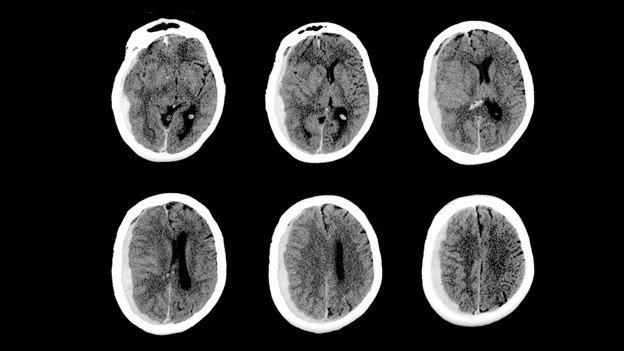

Comprehensive Diagnostic Neuroradiology

Dr. Jain uses advanced MRI, CT, and angiography to diagnose and plan treatment for various neurovascular conditions, ensuring precise interventions tailored to each patient's needs.